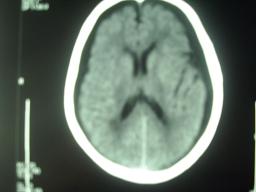

男,90岁,5天前曾摔倒,头颅并未受伤,今天突然头疼,但无呕吐!

ct结果怀疑双侧硬膜下积液!

外伤性硬膜下积液(traumatic subdural effusion, tse)又名外伤性硬膜下水瘤, tse好发于60岁以上老年人,这与老年人存在不同程度脑萎缩、硬膜下间隙增大有关。根据颅脑损伤病史,伤后头痛、头晕、恶心、呕吐等症状,及ct扫描表现为单侧或双侧颅内骨板侧低密度,呈弧形或新月形,与脑组织边界清楚,tse不难诊断

双侧硬膜下积液,个别病例随访观察可形成慢性硬膜下血肿,此例波及范围大,应警惕!